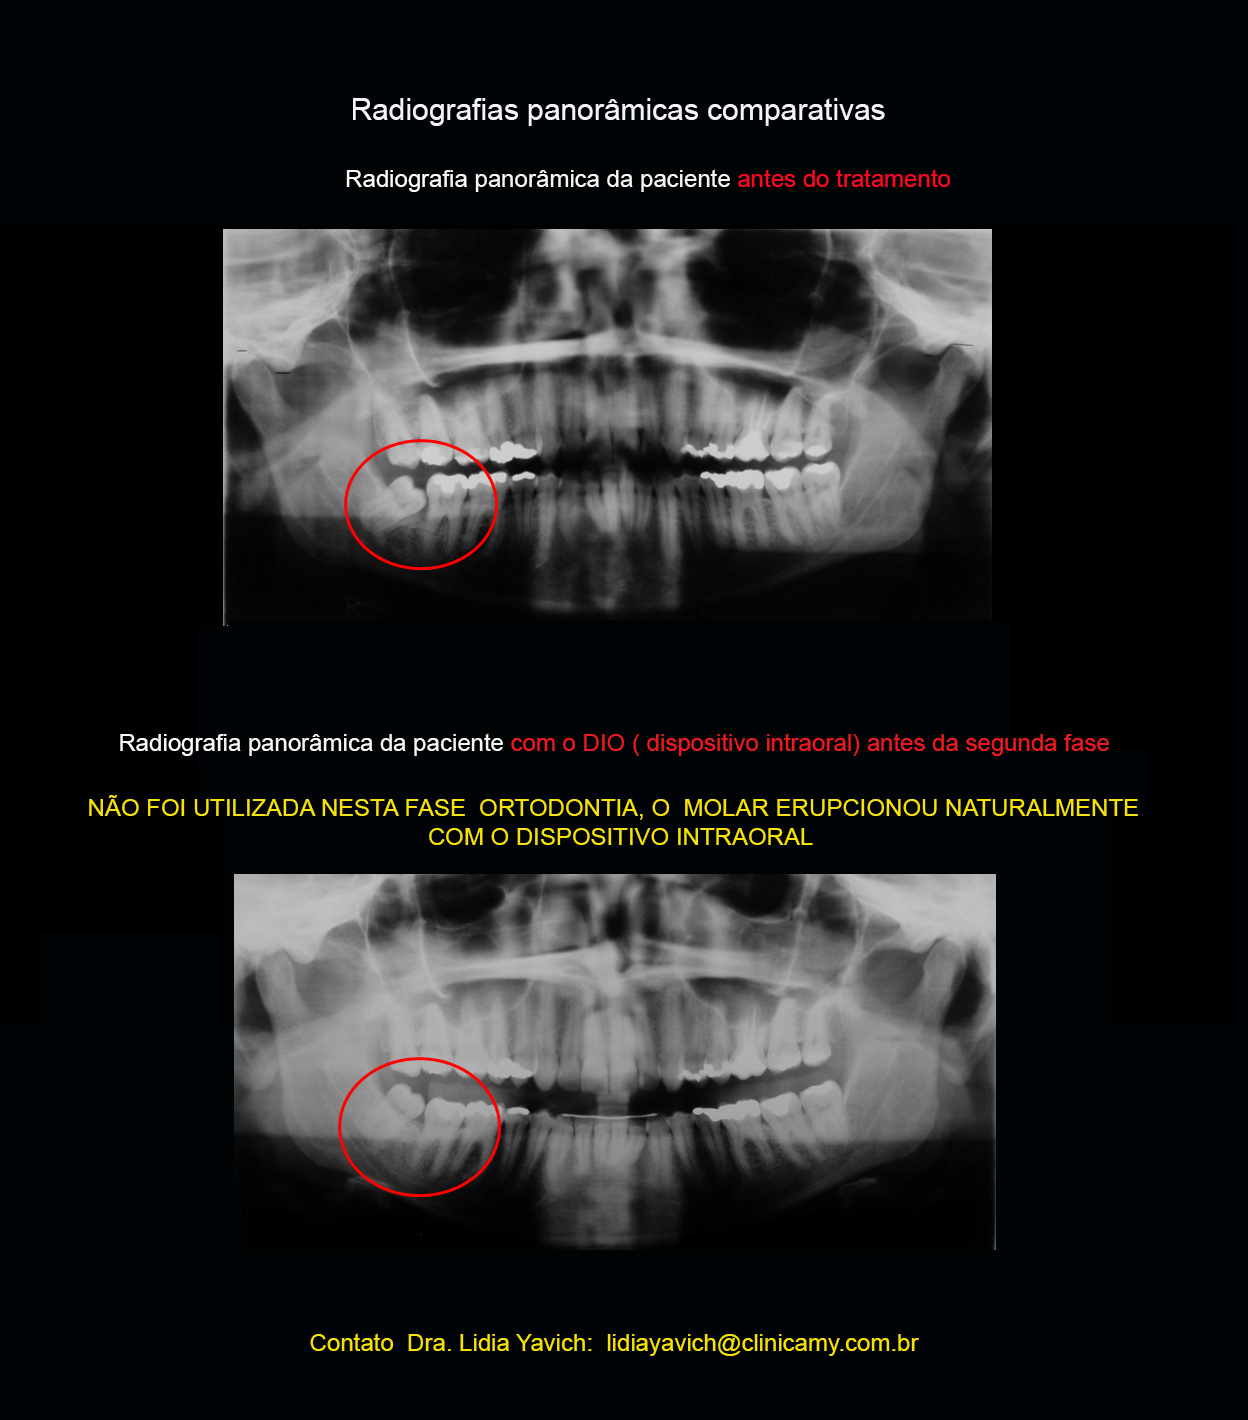

Nota-se o terceiro molar inferior do lado direito (48)encontra-se angulado, e impactado na distal do segundo molar inferior do lado direito.

No pedido da radiografia panorâmica antes de passar para segunda fase, neste caso (ortodontia tridimensional) pode se observar a erupção do terceiro molar inferior direito que estava impactado na distal do segundo molar inferior do lado direito. ( paciente de 31 anos de idade).

Nesta etapa só foi liberado o acrílico do DIO da região do terceiro impactado, devolvendo a dimensão vertical da paciente e permitindo a erupção da peça dentaria.

Comparação da radiografia panorâmica pré-tratamento e após a primeira fase com o DIO (dispositivo intraoral) instalado em posição neurofisiológica.